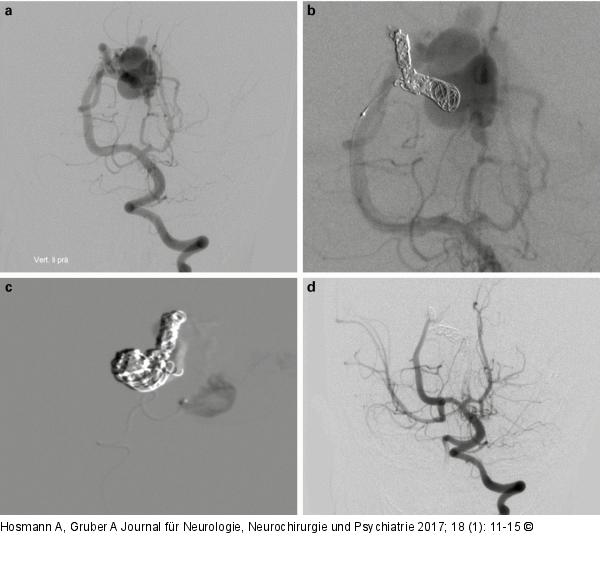

Abbildung 2a-d: Embolisationstechniken Embolisationstechniken: Die Angiographie zeigt eine murale VGM mit prominenten Feedern aus den Aa. choroidea posteriores und einer transmesenzephalen A. perforans (2a). Nach Reduktion des arteriovenösen High-flow-Shuntvolumens durch Embolisation des Haupt-Feeders mittels Coils (2b) wurden die restlichen zwei Feeder komplett mittels Histoacryl embolisiert (2c). Die Abschluss-Angiographie (2d) zeigt eine Totalembolisation der VGM. Durch die Beendigung des Steal-Phänomens kommt es zu einer Blutflussumkehr in der rechten A. communicans posterior mit Füllung der rechten A. cerebri media über die hintere Zirkulation. |